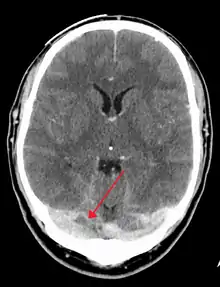

There are various neuroimaging investigations that may detect cerebral sinus thrombosis. Cerebral edema and venous infarction may be apparent on any modality, but for the detection of the thrombus itself, the most commonly used tests are computed tomography (CT) and magnetic resonance imaging (MRI), both using various types of radiocontrast to perform a venogram and visualise the veins around the brain.[2]

Computed tomography, with radiocontrast in the venous phase (CT venography or CTV), has a detection rate that in some regards exceeds that of MRI. The test involves injection into a vein (usually in the arm) of a radioopaque substance, and time is allowed for the bloodstream to carry it to the cerebral veins – at which point the scan is performed. It has a sensitivity of 75–100% (it detects 75–100% of all clots present), and a specificity of 81–100% (it would be incorrectly positive in 0–19%). In the first two weeks, the "empty delta sign" may be observed (in later stages, this sign may disappear).[6]